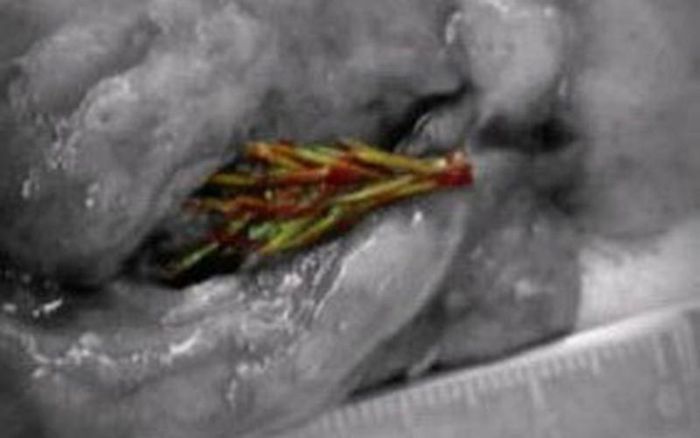

Tuy nhiên, thật bất ngờ, khi mổ ra các bác sỹ phát hiện một cây linh sam nhỏ dài khoảng 5 cm đang mọc ở trong phổi của anh. Đến bây giờ, người ta vẫn chưa lý giải được nguyên nhân tại sao cái cây lại mọc được ở đó.

Hóa ra, Artyom đã nuôi cây trong phổi. Cây linh sam ấy có kích thước khoảng 5cm đang nằm gọn trong lá phổi của anh Artyom.

Các bác sĩ tin rằng Artyom bằng cách nào đó đã hít phải một hạt giống cây linh sam, sau đó nó nảy mầm thành cây nhỏ bên trong phổi của anh. Họ cũng cho rằng Artyom bị ho ra máu là do những chiếc lá cực nhỏ xuyên qua các mao mạch máu.

Cây linh sam có kích thước khoảng 5cm nằm gọn trong lá phổi của anh Artyom.